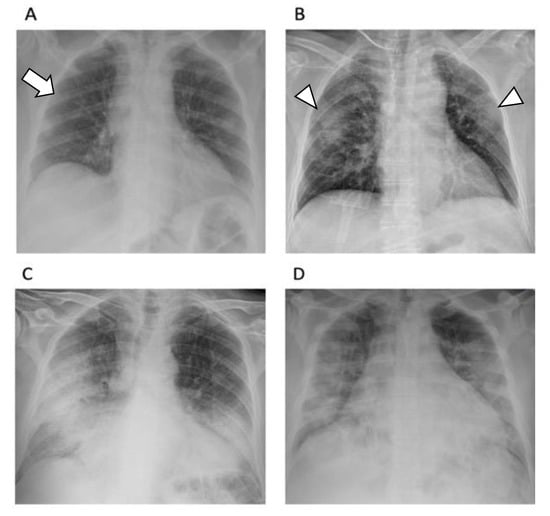

2.6. The Usefulness of Chest X-ray

- Vernuccio, F.; Giambelluca, D.; Cannella, R.; Lombardo, F.P.; Panzuto, F.; Midiri, M.; Cabassa, P. Radiographic and chest CT imaging presentation and follow-up of COVID-19 pneumonia: A multicenter experience from an endemic area. Emerg. Radiol. 2020, 27, 623–632. [Google Scholar] [CrossRef] [PubMed]

- Jacobi, A.; Chung, M.; Bernheim, A.; Eber, C. Portable chest X-ray in coronavirus disease-19 (COVID-19): A pictorial review. Clin. Imaging 2020, 64, 35–42. [Google Scholar] [CrossRef]

- Wong, H.Y.F.; Lam, H.Y.S.; Fong, A.H.-T.; Leung, S.T.; Chin, T.W.-Y.; Lo, C.S.Y.; Lui, M.M.-S.; Lee, J.C.Y.; Chiu, K.W.-H.; Chung, T.W.-H.; et al. Frequency and Distribution of Chest Radiographic Findings in Patients Positive for COVID-19. Radiology 2020, 296, E72–E78. [Google Scholar] [CrossRef] [Green Version]

- Balbi, M.; Caroli, A.; Corsi, A.; Milanese, G.; Surace, A.; Di Marco, F.; Novelli, L.; Silva, M.; Lorini, F.L.; Duca, A.; et al. Chest X-ray for predicting mortality and the need for ventilatory support in COVID-19 patients presenting to the emergency department. Eur. Radiol. 2020, 31, 1999–2012. [Google Scholar] [CrossRef]